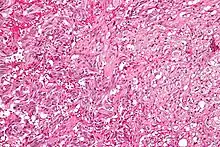

| Micrograph of a gangliocytic paraganglioma. H&E stain. | |

A gangliocytic paraganglioma is a rare tumour that is typically found in the duodenum and consists of three components: (1) ganglion cells, (2) epithelioid cells (paraganglioma-like) and, (3) spindle cells (schwannoma-like).[1]

GP consist of three components (1) ganglion cells, (2) epithelioid cells (neuroendocrine-like), and (3) spindle cells (schwannoma-like). The microscopic differential diagnosis includes poorly differentiated carcinoma, neuroendocrine tumour and paraganglioma.[1]